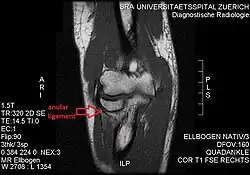

Annular ligament of radius

The annular ligament (orbicular ligament) is a strong band of fibers that encircles the head of the radius, and retains it in contact with the radial notch of the ulna.[1]

The annular ligament is attached by both its ends to the anterior and posterior margins of the radial notch of the ulna, together with which it forms the articular surface that surrounds the head and neck of the radius. The ligament is strong and well defined, yet its flexibility permits the slightly oval head of the radius to rotate freely during pronation and supination.[4][5]

The head of the radius is wider than the bone's neck, and, because the annular ligament embraces both, the radial head is "trapped" inside the ligament which thus acts to prevent distal displacement of the radius.[4] It helps to stabilise the proximal radial head,[6] and the radioulnar joint.[7]